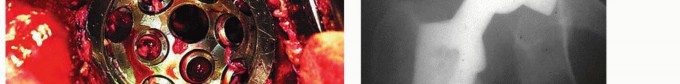

صورة توضيحية لـ هشاشة العظام حول مفصل الورك الاصطناعي تبديل بطانة البولي إيثيلين الحل الأمثل

يتناول هذا المقال الأسباب والتشخيص وخيارات العلاج لهشاشة العظام التي تحدث حول مكونات الحُق الثابتة ![توضيح طبي: هشاشة العظام حول مفصل الورك الاصطناعي تبديل بطانة البولي إيثيلين الحل الأمثل](/media/upload/ad023e43-fc70-4c74-a667-a1eb6d8e107d.jpg) ![توضيح طبي: هشاشة العظام حول مفصل الورك الاصطناعي تبديل بطانة البولي إيثيلين الحل الأمثل](/media/upload/e718bae5-3e04-4049-b408-451d4ebed9ed.jpg) ![توضيح طبي: هشاشة العظام حول مفصل الورك الاصطناعي تبديل بطانة البولي إيثيلين الحل الأمثل](/media/upload/436dcac0-c732-444a-8403-539f5c46ae88.jpg) ![توضيح طبي: هشاشة العظام حول مفصل الورك الاصطناعي تبديل بطانة البولي إيثيلين الحل الأمثل](/media/upload/5295a9df-4504-4c8c-89b3-71233cb41476.jpg) ![توضيح طبي: هشاشة العظام حول مفصل الورك الاصطناعي تبديل بطانة البولي إيثيلين الحل الأمثل](/media/upload/c2411af8-be23-4562-90d6-94b6e9d0c0d9.jpg) ![توضيح طبي: هشاشة العظام حول مفصل الورك الاصطناعي تبديل بطانة البولي إيثيلين الحل الأمثل](/media/upload/eda756a8-6677-4b09-b6f5-3619857552e2.jpg) ![توضيح طبي: هشاشة العظام حول مفصل الورك الاصطناعي تبديل بطانة البولي إيثيلين الحل الأمثل](/media/upload/d199b219-f355-4caf-85c3-a764f4913cb3.jpg) ![توضيح طبي: هشاشة العظام حول مفصل الورك الاصطناعي تبديل بطانة البولي إيثيلين الحل الأمثل](/media/upload/ddd6b344-5b51-450e-8239-8e832b923988.jpg) ![توضيح طبي: هشاشة العظام حول مفصل الورك الاصطناعي تبديل بطانة البولي إيثيلين الحل الأمثل](/media/upload/86786efa-0a81-438c-984d-749c462862d5.jpg) ---